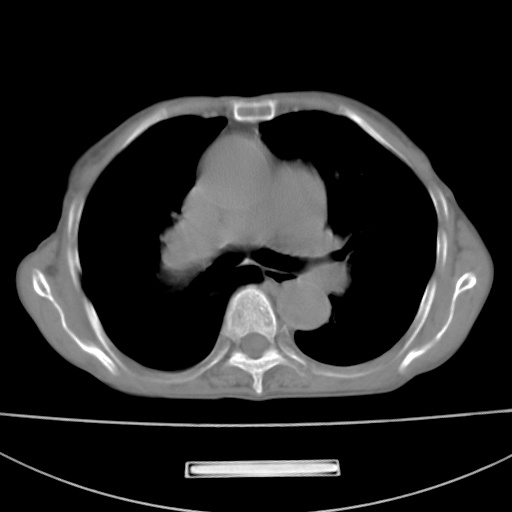

患者 女 67岁,反复咳嗽咳痰2年,加重伴喘及双下肢浮肿1月

陈旧性肺结核、慢性支气管炎、支气管扩张症、肺心症、肺动脉高压。

诸大血管及f肺门血管增粗迂曲.左下肺多发薄壁空腔影.部分非也透亮度增高.薄曾扫描可区分肺气肿类型.考虑1.慢性支气管炎 2.左下肺支气管扩张 3.肺气肿 4 肺动脉高压5.是否有先心病病史

考虑1.慢性支气管炎 2.左下肺支气管扩张 3.肺气肿 4 肺动脉高压

慢支炎、肺气肿、双肺感染、左下囊状支扩。

慢支、肺气肿、肺动脉高压;左下肺囊状支扩并粘液栓形成。